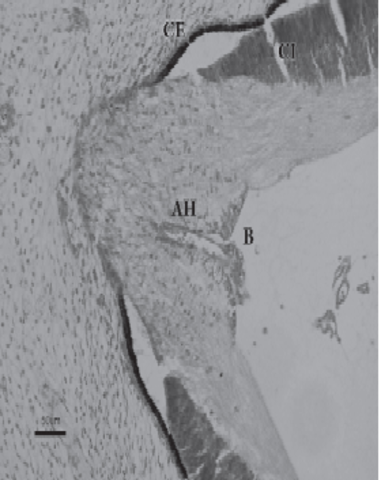

La formación de la hendidura embrionaria conlleva que tanto la capa interna como la externa de la cúpula óptica se continúen con las correspondientes del pedículo óptico. Esta continuidad crea un túnel de paredes superiores a través del cual discurre la arteria hialoidea, rama de la arteria oftálmica, que, de esta manera, penetra en la cúpula óptica sin atravesar ninguna de sus paredes.

Desarrollo del nervio optico

Los axones de las células ganglionares de la retina neurosensorial crecen hacia el pedículo o tallo óptico. De esta manera, la cavidad del tallo se va obliterando. La aparición de los axones en la futura papila se observa en embriones de 16 mm de longitud. Las células del pedículo óptico rodean cranealmente a estas fibras y a la arteria hialoidea

Durante el segundo mes del desarrollo comienza el cierre de la

hendidura embrionaria, debido al crecimiento de los bordes del pedículo óptico. Inicialmente se fusiona la porción intermedia y se extiende en sentido proximal y distal, hasta que a los 20 mm de longitud queda totalmente obliterada. Se observa el quiasma óptico. En la región de la futura papila aparece una acumulación de glioblastos,separando las fibras del nervio óptico del vítreo secundario